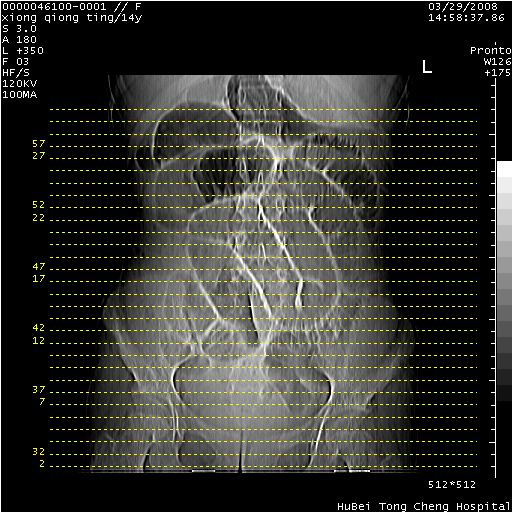

中下腹及盆腔ct轴位平扫+增强扫描(层厚10mm,螺距1.0,重建间隔10mm),图像如下:

(注:患儿检查当日上午9时口服胃肠道对比剂,下午3时许行ct扫描检查,未行对比剂直肠保留灌肠,检查当日患儿腹泻)